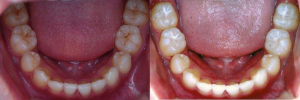

A:孩子6岁左右时,在第二乳磨牙后萌出的牙,叫“第一恒磨牙”,因其在6岁左右萌出,习惯称为“六龄齿”或“六龄牙”。

A:六龄齿牙尖多,牙尖与牙尖之间的窝沟多,且又深又窄,容易藏垢纳污,不易清洁,所以龋坏率高。

03 为六龄齿做窝沟封闭

窝沟封闭在龋齿发生之前,填平咬合面较深的窝沟,使食物残渣和菌斑不易堆积,达到预防龋齿的效果。窝沟封闭的方法:通过清洁牙面、酸蚀、冲洗、干燥、涂封闭剂、固化几个步骤来完成。